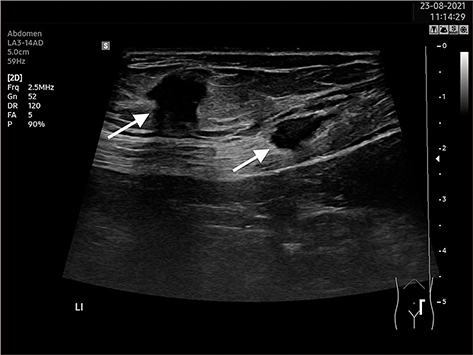

Op de echo is bij de pijnlocatie in het diepe subcutane vet een echoarme, heterogene en niet-comprimeerbare laesie van 15 x 10 x 9 mm te zien, met 1 cm caudaal hiervan, oppervlakkig in de buikspier, een echoarme ovale heterogene laesie van 6 x 13 mm [figuur]. Het lijkt om 2 endometriomen te gaan. Haar voorgeschiedenis bevatte geen klachten die bij endometriose passen. Na chirurgische behandeling is ze klachtenvrij.

Figuur | Op de echo van de patiënte zijn 2 endometriomen te zien in de subcutis en in de buikspier.

Echoscopie is voldoende voor het stellen van de diagnose. Het endometrioom heeft een echografisch beeld van een rond of ovaal heterogeen echoarm gebied zonder flow, waarbij we intern typische echorijke delen en fibrotische veranderingen kunnen zien [figuur]. Vier procent van de patiëntes heeft dus geen zwelling, maar wel pijn. Na overleg met de patiënte kan al dan niet een echo worden gemaakt.